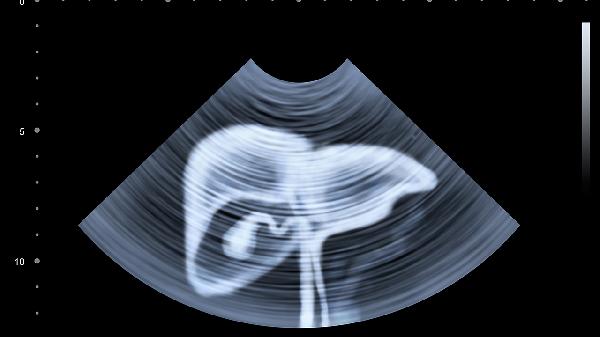

产褥感染或手术伤口未愈可能引发盆腔炎,表现为持续坠痛伴发热、异常分泌物。需检查血常规及超声明确,轻症可口服头孢克肟等抗生素,严重者需静脉给药。哺乳期用药需告知避免使用喹诺酮类影响婴儿骨骼发育。